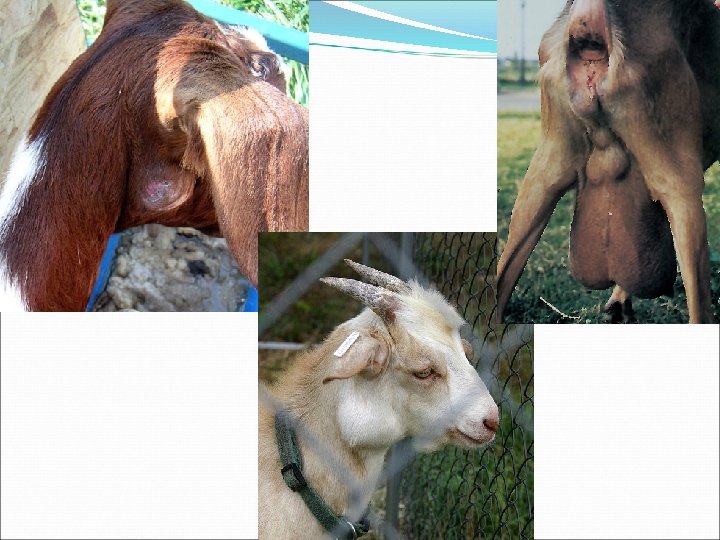

Clinical Features of CLA �Pyogranulomatous lesions (abscesses) in 2 main forms �External form � Aka ‘superficial’ or ‘cutaneous’ � Characterized by abscessation of external lymph nodes �Internal form � Aka ‘visceral’ � Abscesses in internal llnn. & other organs �BOTH forms may coexist in same animal!

External CLA �Most common form in GOATS �Superficial lymph node abscesses �Diameters of 3 -15 cm �Principal lymph nodes affected �Goats: head & neck � Submandibular, parotid, prescapular �Sheep: torso � #1: Prefemoral, #2: prescapular

Summary of CLA by Species Sheep Goats Most common form Internal External llnn. most affected Torso: Prefemoral Prescapular Head/neck: Submandibular Parotid Prescapular Abscess content Caseated, ‘onion layered’ Uniform, pasty, green